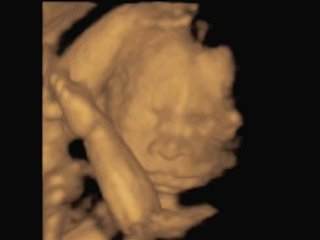

Ultrasound 3D 015

Fetal Studio offers affordable and professional access to prenatal ultrasound, limited medical surveys and level 1 ultrasounds, also the best 3D & 4D imaging quality available on the market.